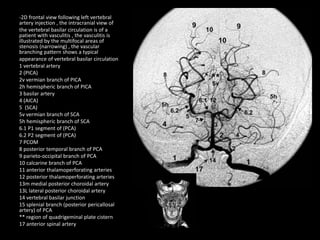

-2D frontal view following left vertebral

artery injection , the intracranial view of

the vertebral basilar circulation is of a

patient with vasculitis , the vasculitis is

illustrated by the multifocal areas of

stenosis (narrowing) , the vascular

branching pattern shows a typical

appearance of vertebral basilar circulation

1 vertebral artery

2 (PICA)

2v vermian branch of PICA

2h hemispheric branch of PICA

3 basilar artery

4 (AICA)

5 (SCA)

5v vermian branch of SCA

5h hemispheric branch of SCA

6.1 P1 segment of (PCA)

6.2 P2 segment of (PCA)

7 PCOM

8 posterior temporal branch of PCA

9 parieto-occipital branch of PCA

10 calcarine branch of PCA

11 anterior thalamoperforating arteries

12 posterior thalamoperforating arteries

13m medial posterior choroidal artery

13L lateral posterior choroidal artery

14 vertebral basilar junction

15 splenial branch (posterior pericallosal

artery) of PCA

** region of quadrigeminal plate cistern

17 anterior spinal artery